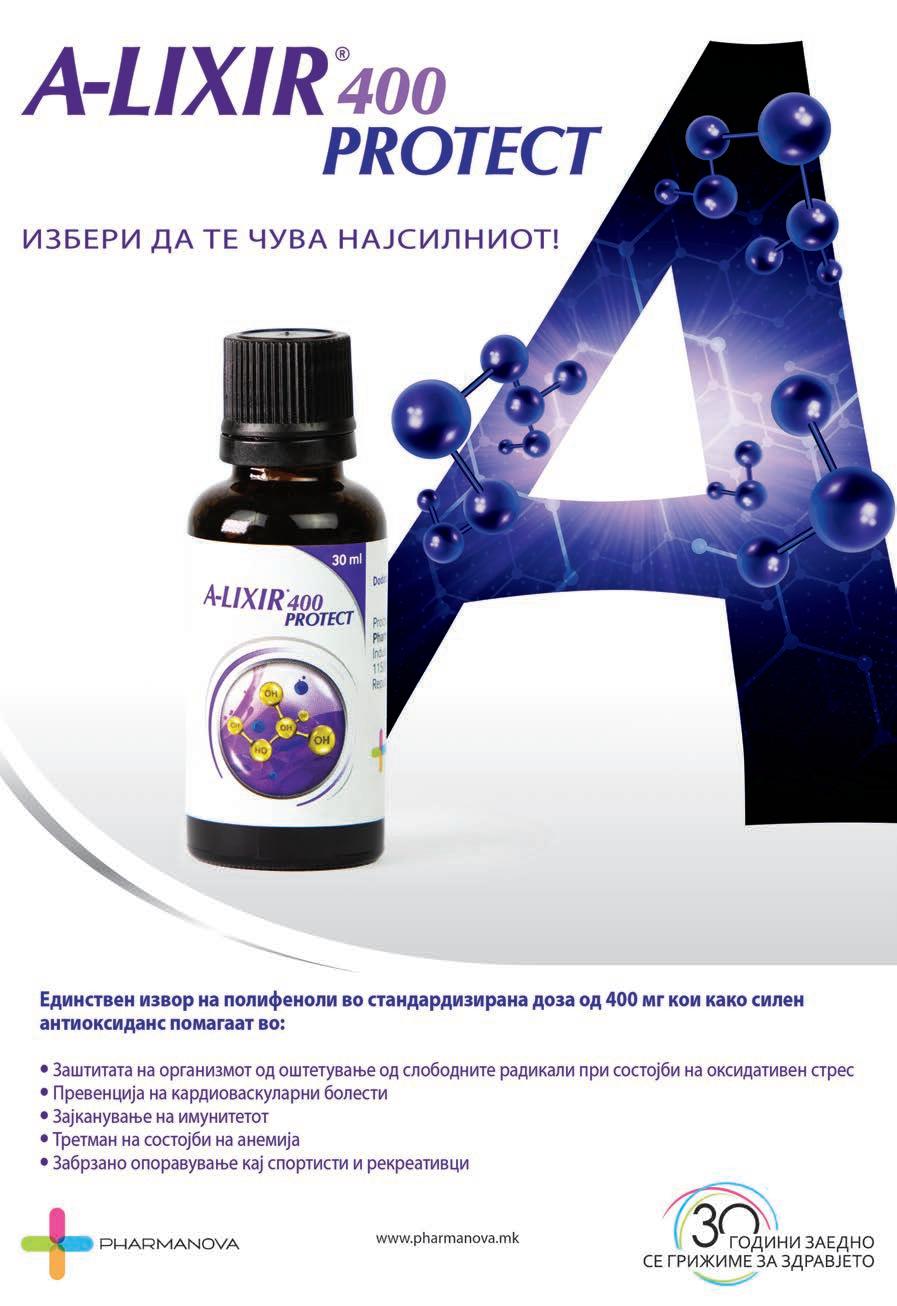

- стандардизирање и титрирање на полифеноли